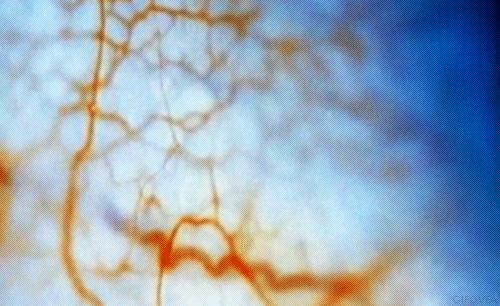

血液循環,是指血液從心臟出發,通過動脈輸送到全身,再借助靜脈迴流心臟的過程。

高血糖會導致血液黏稠度變高,引起血管內皮損傷,血管基膜增厚,紅細胞聚集,血小板黏附在血管內膜下,最終形成微血栓或微血管閉塞。

比如,糖尿病可引發身體多處的微循環障礙,當問題出現在眼部,會導致糖尿病視網膜病變;當血液受阻於腎臟,則會患上糖尿病腎病。可見,控制血糖水平纔是解決循環障礙的根本。